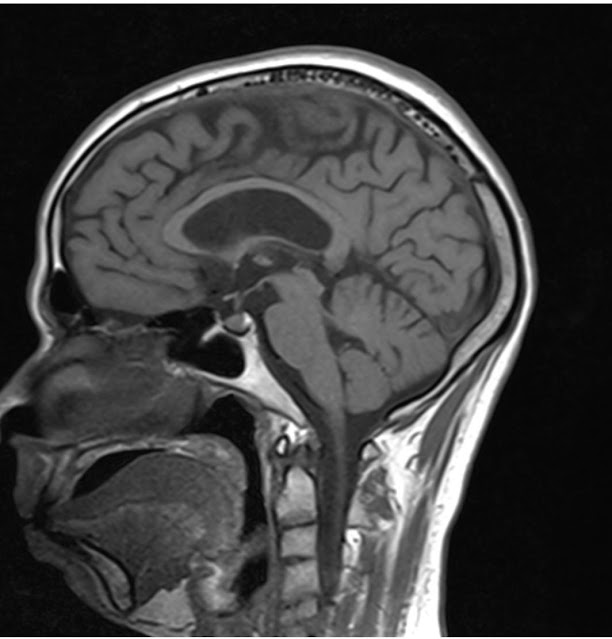

A 32 year old man with a history of consuming large amounts of alcohol since the past 3 years presented with an acute onset dementia, cognitive impairment. His last alcohol intake was 3 months back, His MRI brain revealed diffusely thinned out corpus callosum.

MRI BRAIN: showing Diffusely thinned out corpus callosum